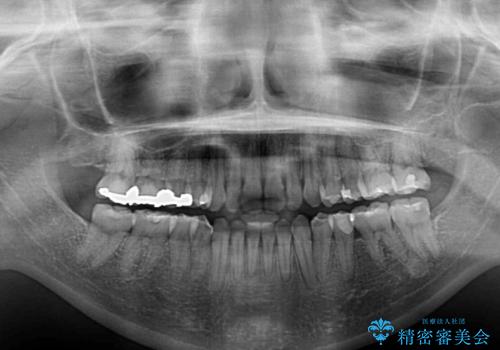

治療途中で出産されたこともあり、当初予定よりも終了までに期間がかかってしまいました。

舌を前方に突出する癖があったため、上下前歯がなかなか接触しなかったことも治療期間が伸びた要因です。